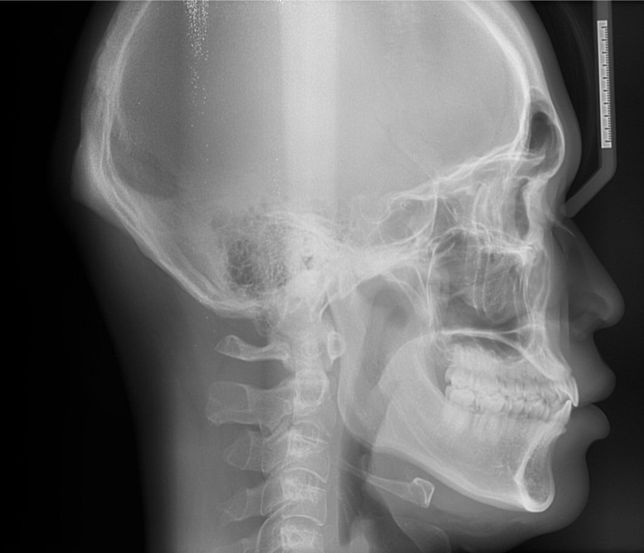

- 치과의료상담Q. 제 옆모습을 가끔 보면 턱이랑 입이 나온것같아보이는데 전문의가 평가하기에도 그런지 알고싶어요질문1. 제 옆모습을 가끔 보면 턱이랑 입이 나온것같아보이는데 전문의가 평가하기에도 그런지 알고싶어요가끔 사진찍히거나 거울볼때 옆모습이 입이랑 턱이 남들보다 나온것같다는 생각이들거든요 이런게 주걱턱인가? 이게 치과에 문의하는게 맞는지 모르겠지만 전문의님 개인평가를 듣고싶어요~ 나중에 구강악쪽 양악수술 상담한번 받아보려고요질문2. 만약 입만 넣는다면 발치없이 인비절라인 같은 투명교정으로도 가능할까요?질문3. 제 앞니 치근이 짧나요?이미지가 포함된 질문이에요.

- 치과의료상담Q. 중안면부 꺼짐있는경우 양악을 하면 개선이 되나요?중안면부 꺼짐있는 경우 미용적인 목적으로 양악수술을 하면 개선이 되나요?보통은 이런경우 코수술을 하게되나요?치아 교합은 정상인데 일자목이라서 그런건지모르겠지만 옆모습을 봤을때 입체적이지 않고 약간 1자 모습? \\모양 이여서 콤플렉스입니다.오히려 이런경우 부작용이 크나요?자료가 부족하겠지만 그냥 의사님들 개인생각 적어주시면 도움이될것같습니다지인분들마다 평가하시는게 달라서 저스스로도 수술고민하는게 맞는지 잘모르겠습니다 (남자라서 괜찮다, 전혀모르겠다, 약간 턱이 나온것같다, 입이나온거다,연예인할것도 아닌데 왜그러냐 등등)그리고 제가 살짝 팔랑귀라서 고민하게되네요이미지가 포함된 질문이에요.

- 이비인후과의료상담Q. 거북목인가요? 아님 그냥 하악턱이 돌출되어서 그런건가요?평소에 그냥 편한자세로 걸어다니는데 주변에서 허리피고 턱내리고 걸으래요ㅠ뭔가 제가 턱을 들고다니는것같기도 하고 아닌것같기도 해서 잘모르겠어요질문1)거북목이면 턱도 들고다니나요?질문2)턱이나와서 그렇게 보이는건지 아니면 거북목증상 있어서 그런건지 알수있을까요? 대략적으로라도요허리피고 가슴피고 턱내리고 다니면 뒷목부근이 땡겨서 불편해요질문4)거북목이면 어떤운동하면 교정가능할까요?이미지가 포함된 질문이에요.

- 성형외과의료상담Q. 턱 돌출 성형 및 구강악 수술에대한 문의아하에 치과쪽에 질문을 자주애용해서 여기에 의사님들 개인적인 의견을 여쭙고자 질문남깁니다구강악외과에서 턱정밀상담 결과 하관평균길이가 성인남성평균보다 길고 돌출되었다고 들은 이후에 신경이 쓰여 수술 질문좀 하고싶습니다의사분께서는 기능적으로 이상은 없다고 수술을 권장하지는 않았습니다 미용적인거라고해서..아하 의사님들 개인적인 생각으로는 하관 수술하면 괜찮아질까요?그리고 돌출된 턱만 따로 수술가능한가요?수술이란게 기능개선이 주목적인데 저는 미용목적이니 괜히 할려고 고민하는게 아닌가 걱정되어서요양악수술이나 하관수술해서 괜히 후회할까봐서요실제와 사진은 다르겠지만 ct와사진만보고 개인적은 의견 적어주시면 참고하도록 하겠습니다댓글달아주시는 의사님들 감사합니다^^이미지가 포함된 질문이에요.